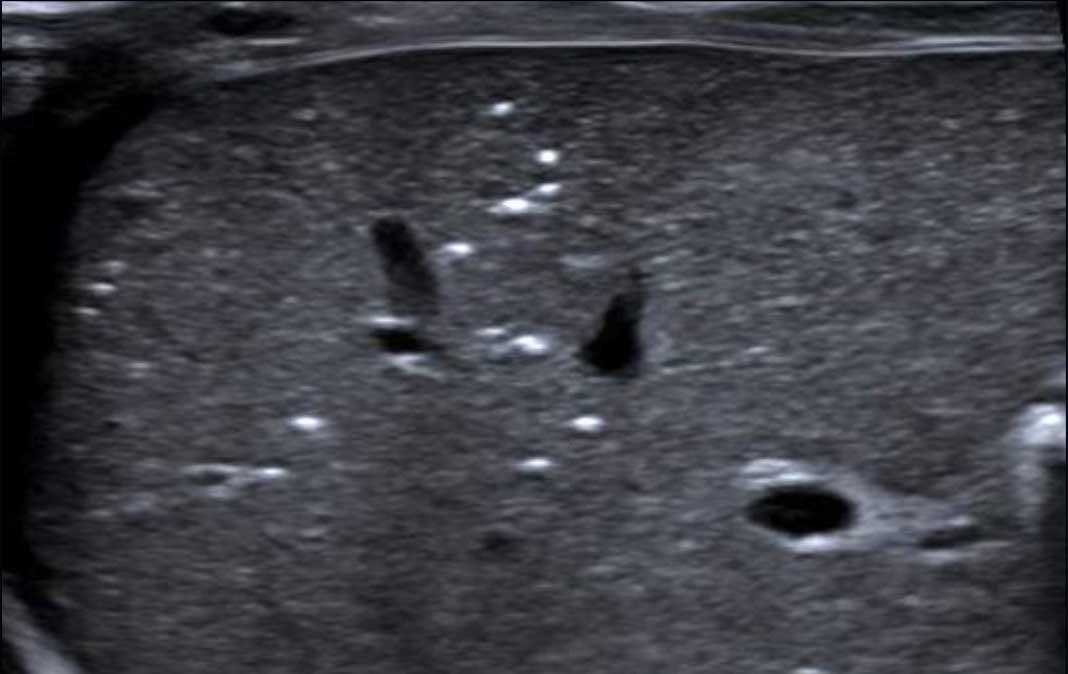

Hình ảnh

Bé trai 4 tháng tuổi đã phẫu thuật tim bẩm sinh phức tạp, hiện có phân lẫn máu.

X-quang bụng cho thấy khí trong thành ruột (pneumatosis) (mũi tên).

Dấu hiệu này cũng được thấy trên siêu âm ở đoạn ruột bên trái, trong khi đoạn ruột lành bên phải cho thấy các phản âm hơi bình thường.